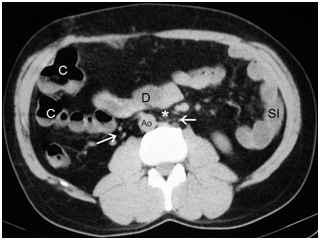

Figure 6Aorta on the right (Ao) and intestinal malrotation because the duodenum (D) does not pass between the aorta and the superior mesenteric artery (asterisk). Vascular structures that may correspond to infrarenal IVC cannot be identified, only multiple retroperitoneal serpiginous vessels (arrows), presumably venous, are identified close to the aorta.

5. Infrarenal IVC unidentifiable, multiple retroperitoneal serpiginous vessels, presumably venous, are identified close to the aorta (Figure 8).

7. Intestinal malrotation: the duodenum does not pass between the aorta and the superior mesenteric artery, Treitz’s angle is not visualized, the colon lies in the right hemiabdomen, and the small intestine in left hemiabdomen (Figures 4-6).